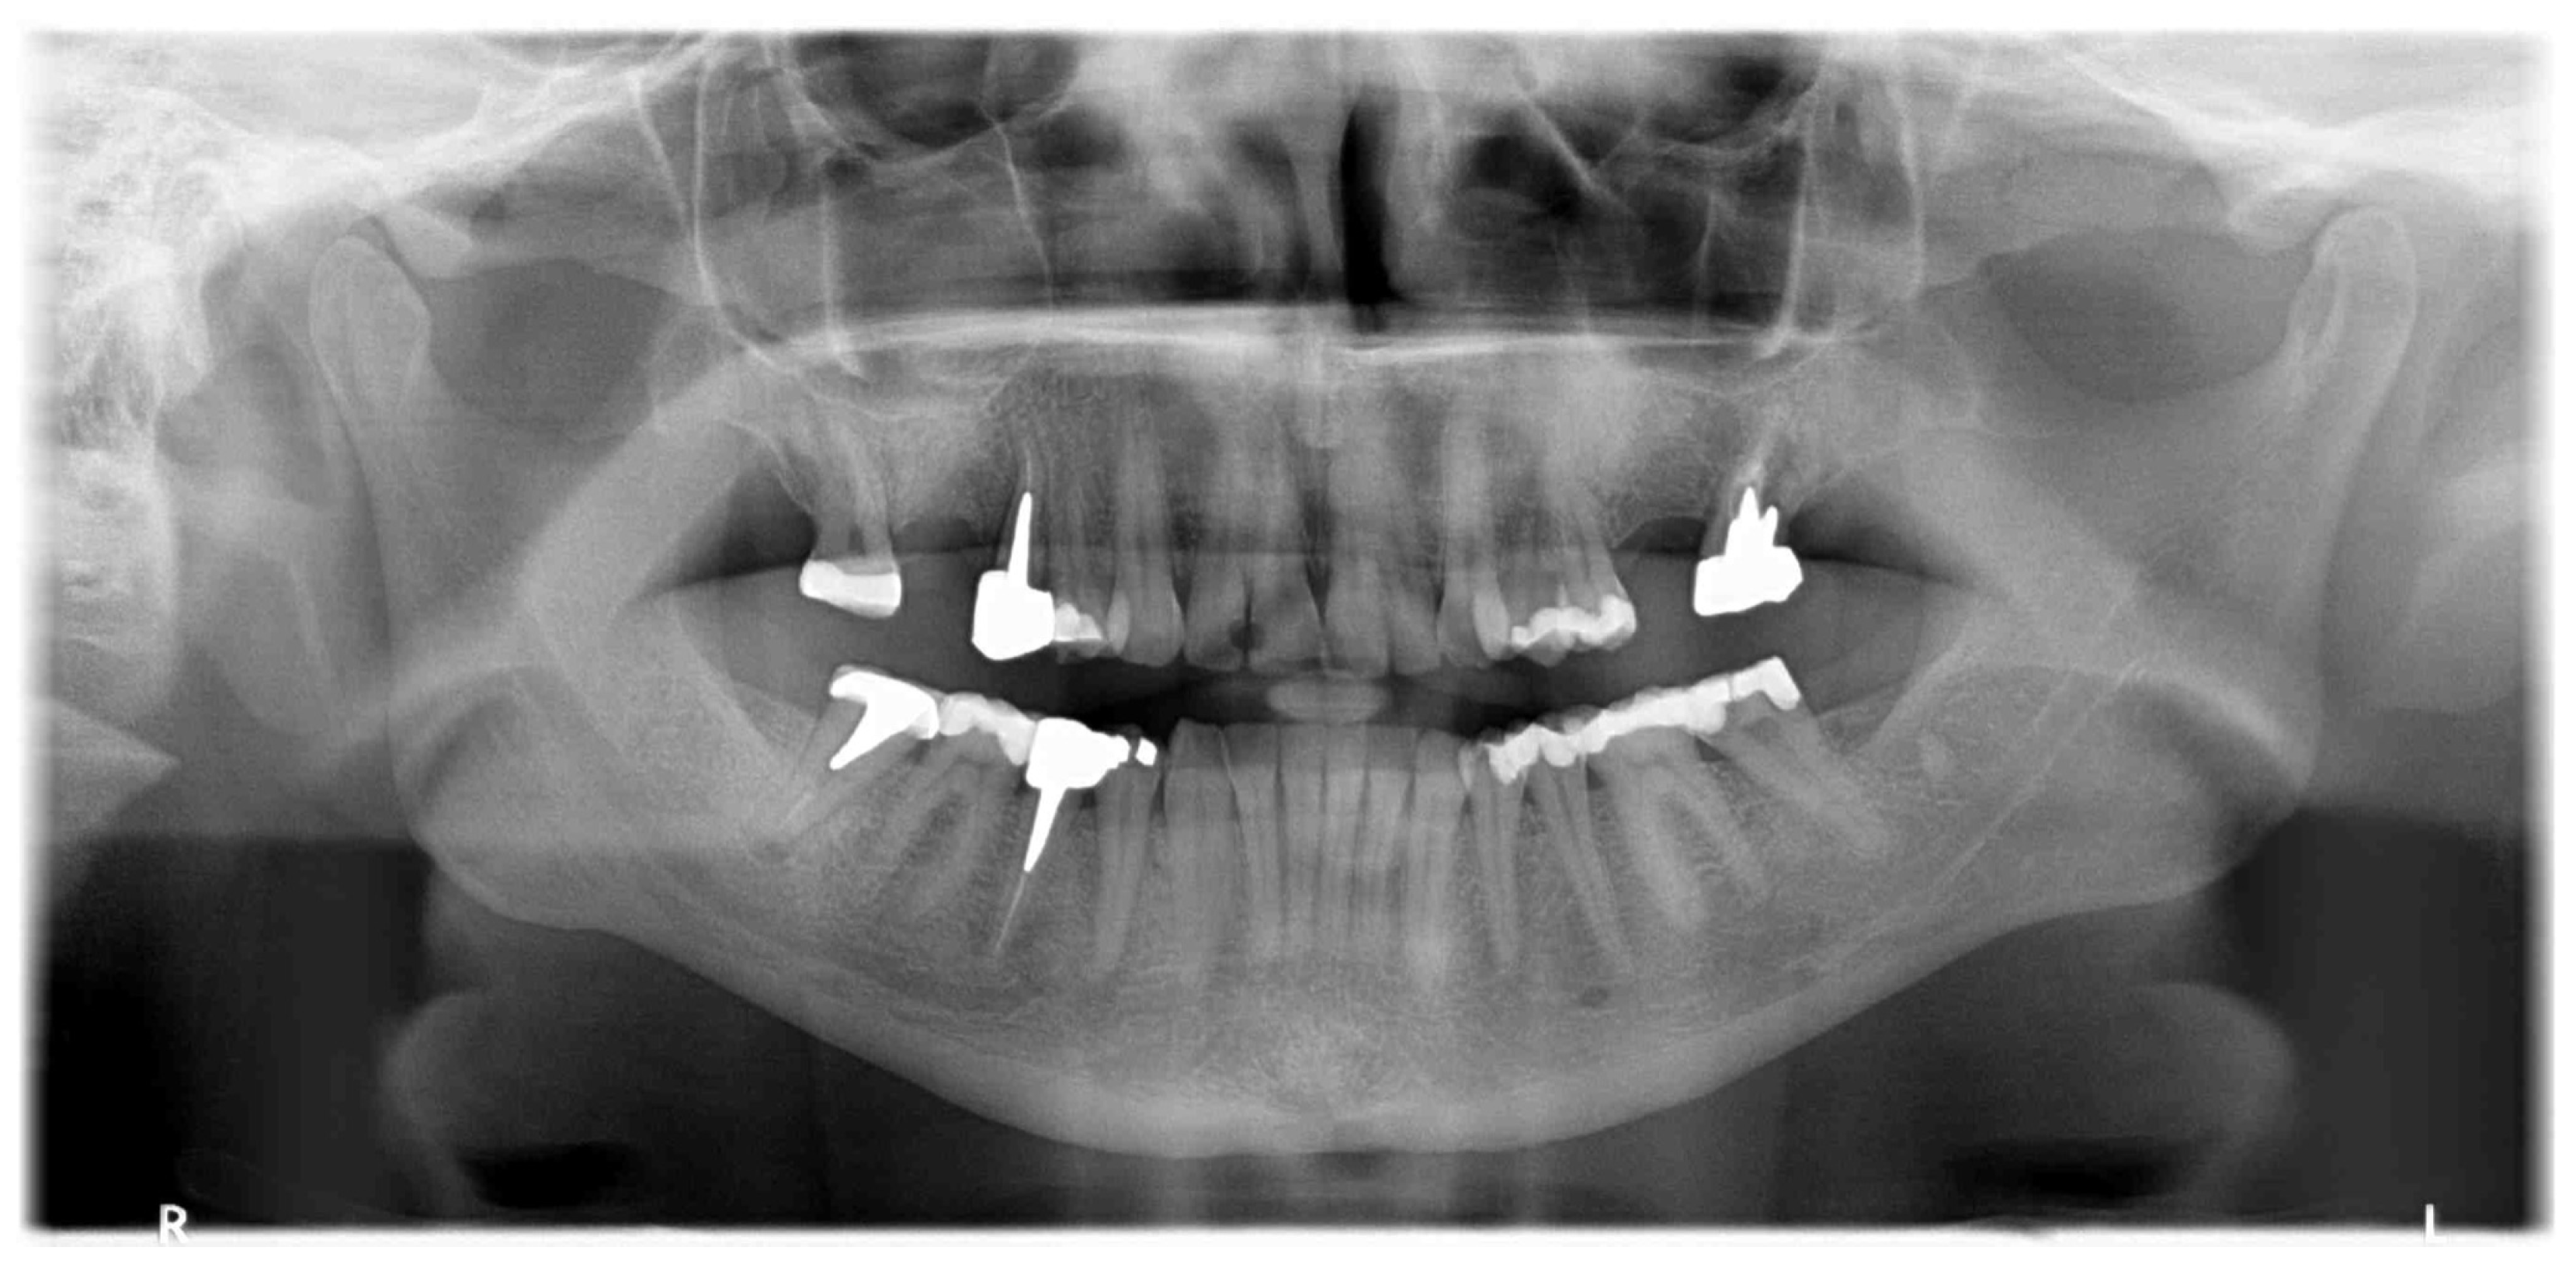

Implant rehabilitation was suggested. For this, a panoramic X-ray was performed, and it showed a homogeneous radiopacity in the left upper jaw, with feathered edges of about 10 mm in dimension (Figure 2).

Figure 2.

Orthopanoramic X-ray showing radiopacity in left upper jaw.